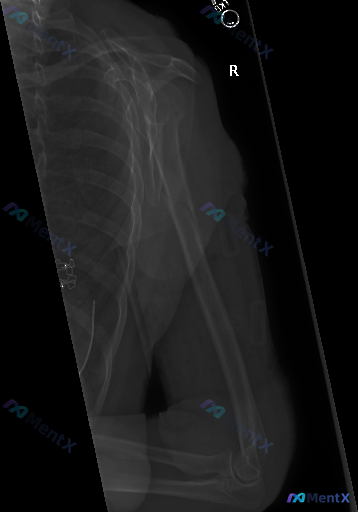

整理到一张放射影像学图像资料,先和大家同步客观信息: 检查类型: 右侧肩关节及肱骨全长X线平片(正位/前后位投影) 影像学观察到的表现: 1. 骨骼方面:右侧肱骨干中下段可见清晰锐利的骨折线,断端有明显错位,远端向外侧移位且存在重叠,提示短缩畸形;肩胛骨、锁骨、肱骨头、肱骨远端与尺桡骨近端构成的关节...